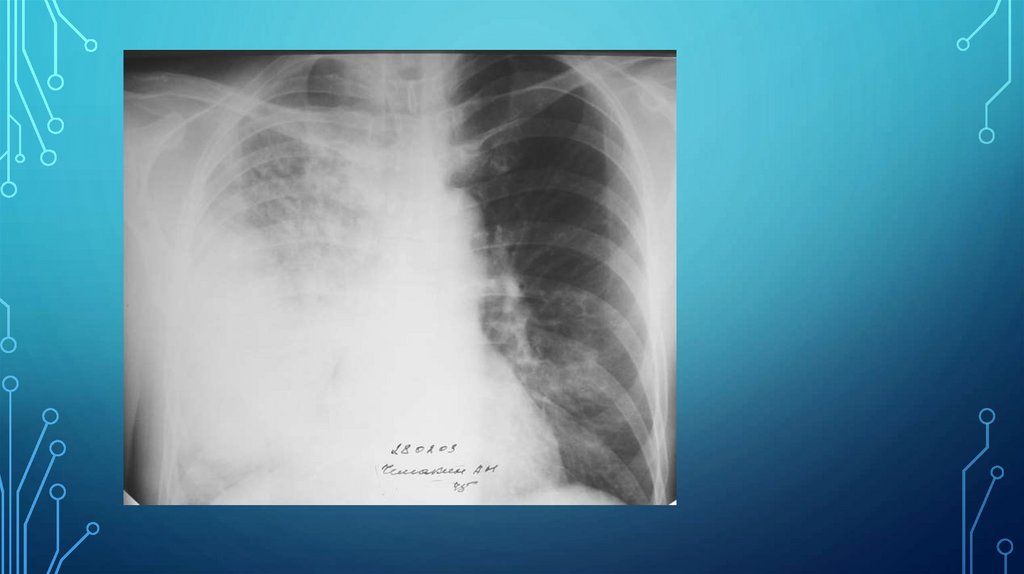

А)Свободная жидкость в плевральной полости в прямой проекции при

вертикальном положении больного проявляется однородным затененим нижне-латеральной

части легочного поля с косой верхней границей (линия Эллиса-Дамуазо), контур ее нечеткий,

при вдохе смещается вниз, при выдохе – вверх